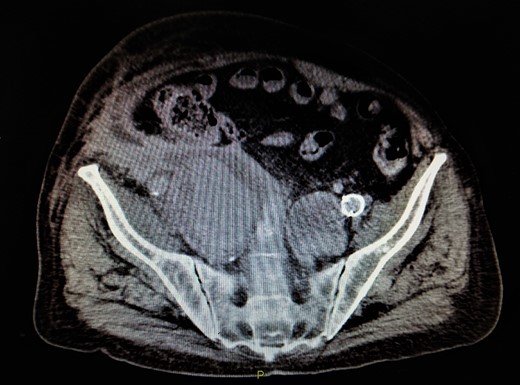

A 78-year-old man was referred in our vascular unit due to an 8.8 cm right IIAA. His medical history included arterial hypertension, diabetes mellitus (non-insulin dependent), right hemicolectomy for adenocarcinoma of ascending colon and EVAR of abdominal aortic aneurysm with Anaconda stent graft (Anaconda, Vascutek, Scotland) 6 years ago followed by deployment of extensions in external iliac arteries with coverage of internal iliac arteries 1 year later in another facility. The patient did not refer any buttock claudication or intestinal disturbances during follow-up. The last control with computed tomography angiography was performed 4 years ago (CTA) depicting a right IIAA, 4.3 cm, which was decided to be managed conservative due to his medical comorbidities. A contrast-enhanced CT was performed in our unit which revealed an 8.8 cm right IIAA with the presence of two runoff vessels deep in the pelvis with direction to the gluteal muscles (Fig. 1). An endovascular embolization of the aneurysm was decided due to his medical history. The patient was fully informed for the endovascular repair, the possible complications of the operation and written consent was obtained.

Contrast-enhanced CT depicted an increase of right IIA to 8,8 cm with type II endoleak from two runoff vessels deep in the pelvic cavity.